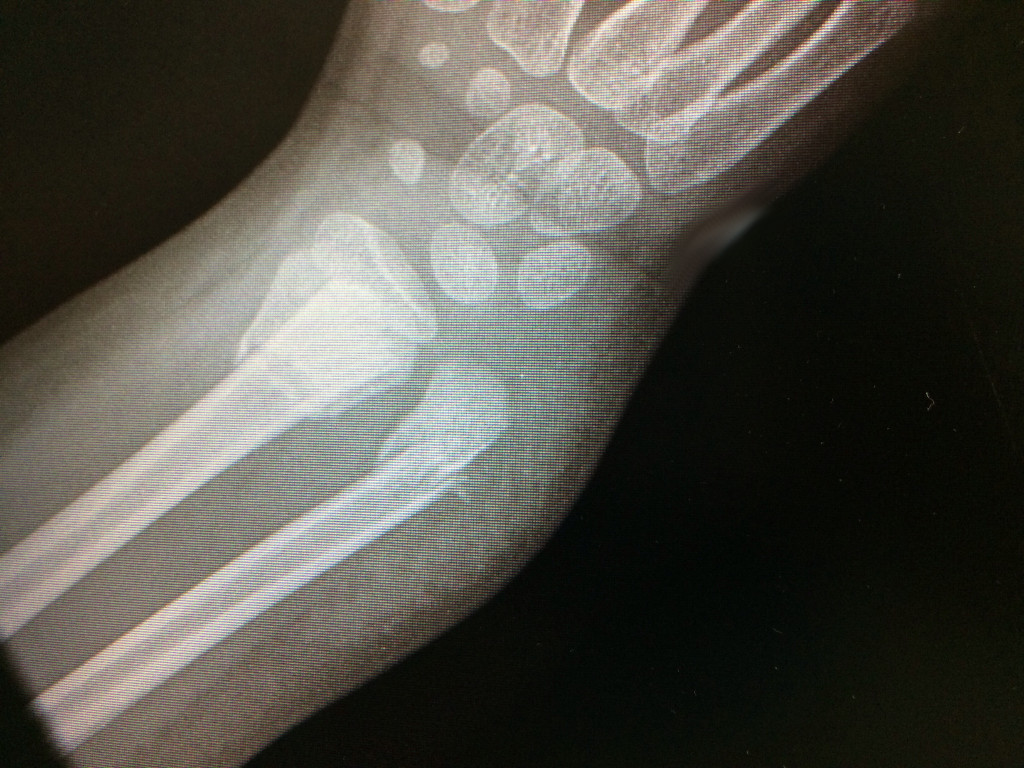

L'examen physique et les radiographies sont essentiels pour le diagnostic précis de ces fractures et pour orienter le traitement. Les radiographies standards peuvent être complétées par un examen scanner si la fracture est intra-articulaire.

- Cas 1 (fractura de radio distal intraticular tratada con placa)

- Cas 2 (fractura conminuta de radio tratada con placa larga)